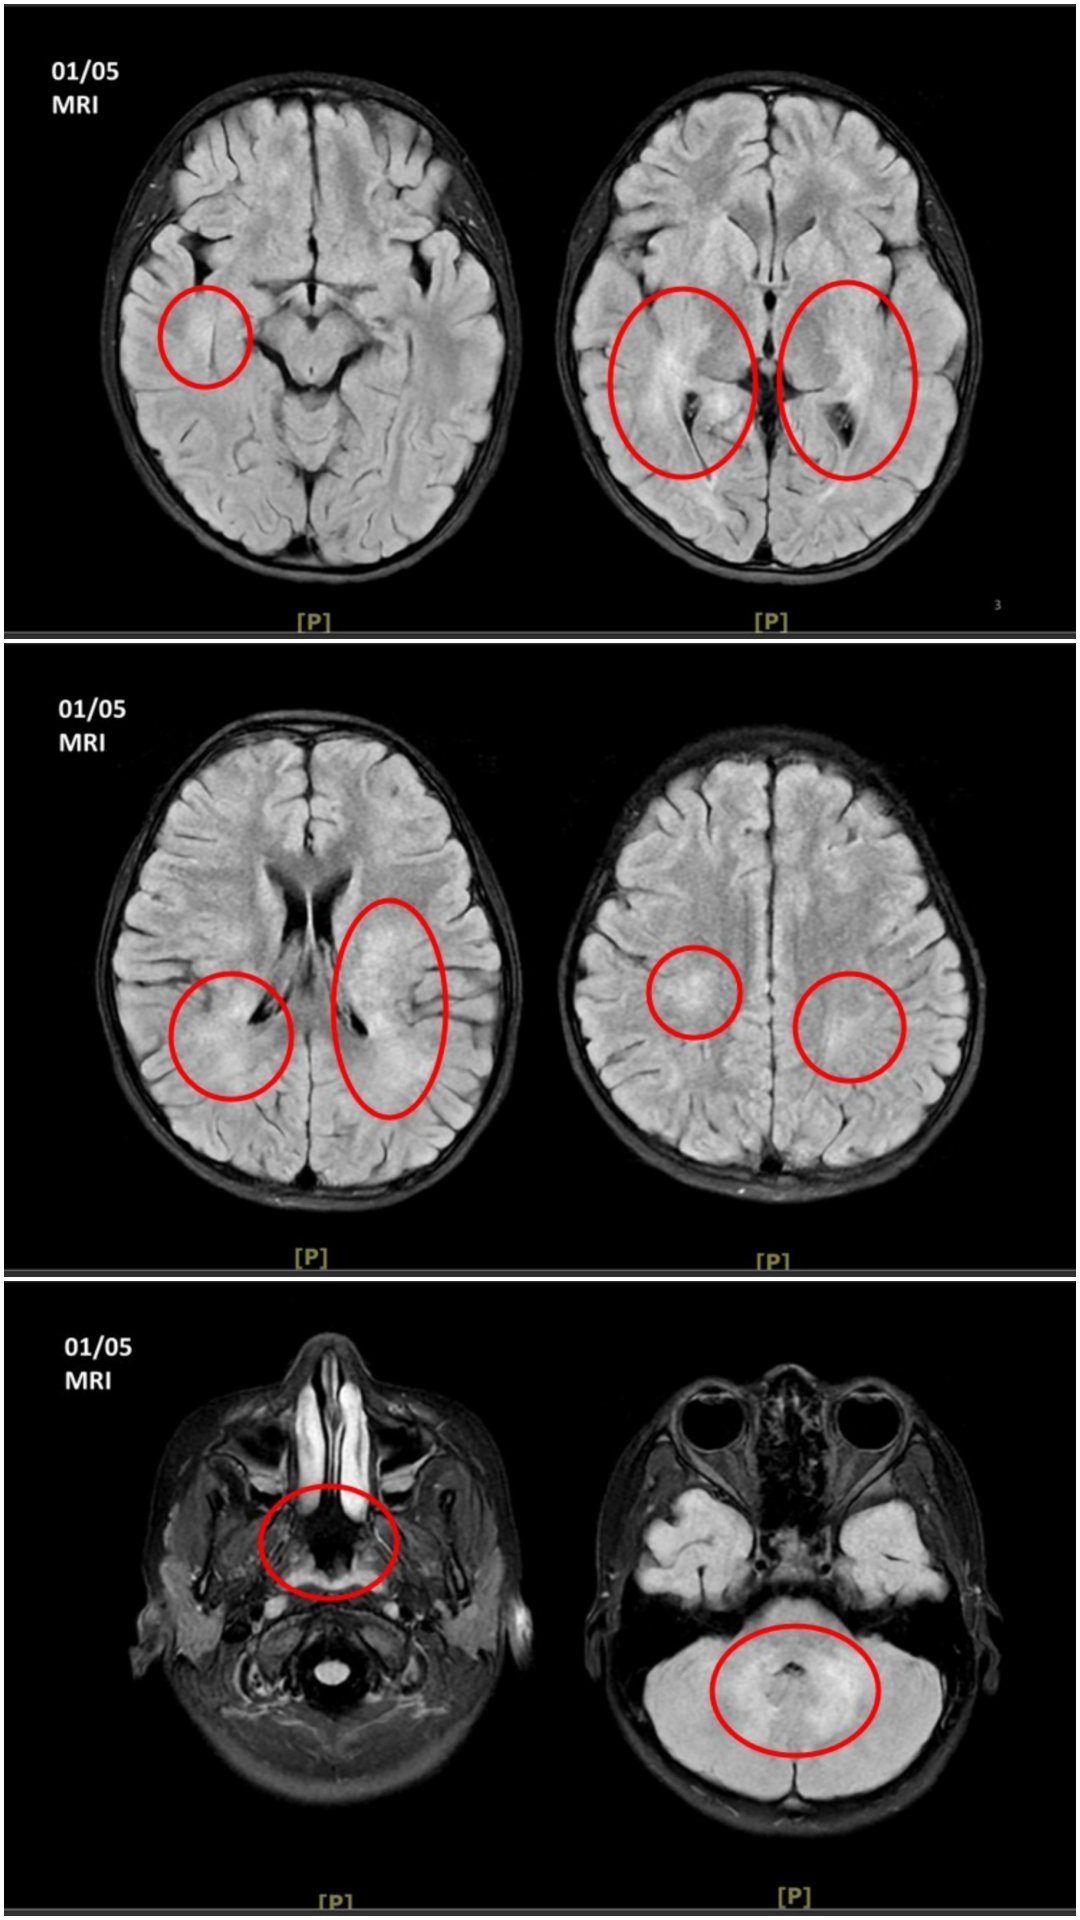

王傳育主任指出,女童當時血壓明顯偏高,心跳也較慢,醫療團隊擔心已有腦壓升高或顱內病變,立即安排住院,並同步給予降低腦壓治療與核磁共振掃描。檢查結果顯示,小腦、視丘及大腦白質、皮質下都可見異常訊號,符合急性散播性腦脊髓炎的影像表現。